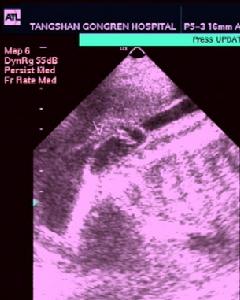

2.CT、MRI掃描顯示脊柱裂及脊髓、神經的畸形,以及局部粘連等病理情況。